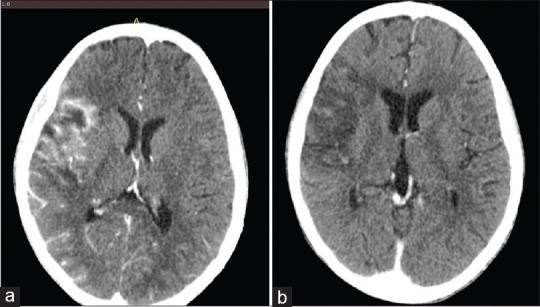

摘要:脾脓肿是一种危及生命的疾病,在儿童中非常罕见。患上脾脓肿通常有感染病灶或免疫缺陷等诱发因素。英文文献中仅报道过一例成人脾脓肿合并脑脓肿的病例。因此,我们报告了一例 11 岁男孩的病例,他原本身体健康,但出现发热和体重减轻 2 个月,右上腹痛、呕吐、下腹压痛 1 周,后来在就诊前 2 天出现左侧偏瘫和右侧面瘫。腹盆腔超声扫描、腹部和头颅计算机断层扫描证实了脾脓肿和右侧脑内脓肿的诊断。随后,他接受了经皮超声引导的脾脓肿引流术,但引流不成功,不得不进行脾切除术,并积极使用抗生素治疗。本报告旨在强调有必要加强对免疫力低下儿童脾脓肿的怀疑,并增加对这种罕见儿童疾病的管理知识。我们的结论是,脾脓肿并发脑内脓肿是一种罕见但危及生命的疾病,可通过脓肿引流和积极的抗菌治疗进行治疗。

Abstract: Splenic abscess is a life-threatening condition, which is very rare in children. There is usually an infective focus or pre-disposing factors such as immunodeficiencies towards developing splenic abscesses. Only one case of splenic abscess with brain abscesses in an adult has been reported in the English literature. We, therefore, report a case of an 11-year-old boy who was otherwise healthy, but presented with fever and weight loss for 2 months, right upper abdominal pain, vomiting, hypochondrial tenderness for 1 week and later on developed a left hemiplegia and right facioparesis 2 days before presentation. Diagnosis of splenic abscess and right intracerebral abscesses was confirmed with abdominopelvic ultrasound scan and abdominal and cranial computerised tomographic scans. He subsequently had percutaneous ultrasound-guided drainage of the splenic abscess which was not successful necessitating splenectomy with aggressive antibiotics treatment to which the patient responded with resolution of the brain abscesses and recovery of power in affected limbs. This report aimed to highlight the need for increased suspicion of splenic abscesses in children who are apparently immunocompetent and to add to the knowledge of management of this rare condition in children. We conclude that splenic abscess with intracerebral abscess is a rare but life-threatening condition which is amenable to treatment with drainage of abscess and aggressive guided antimicrobial therapy.